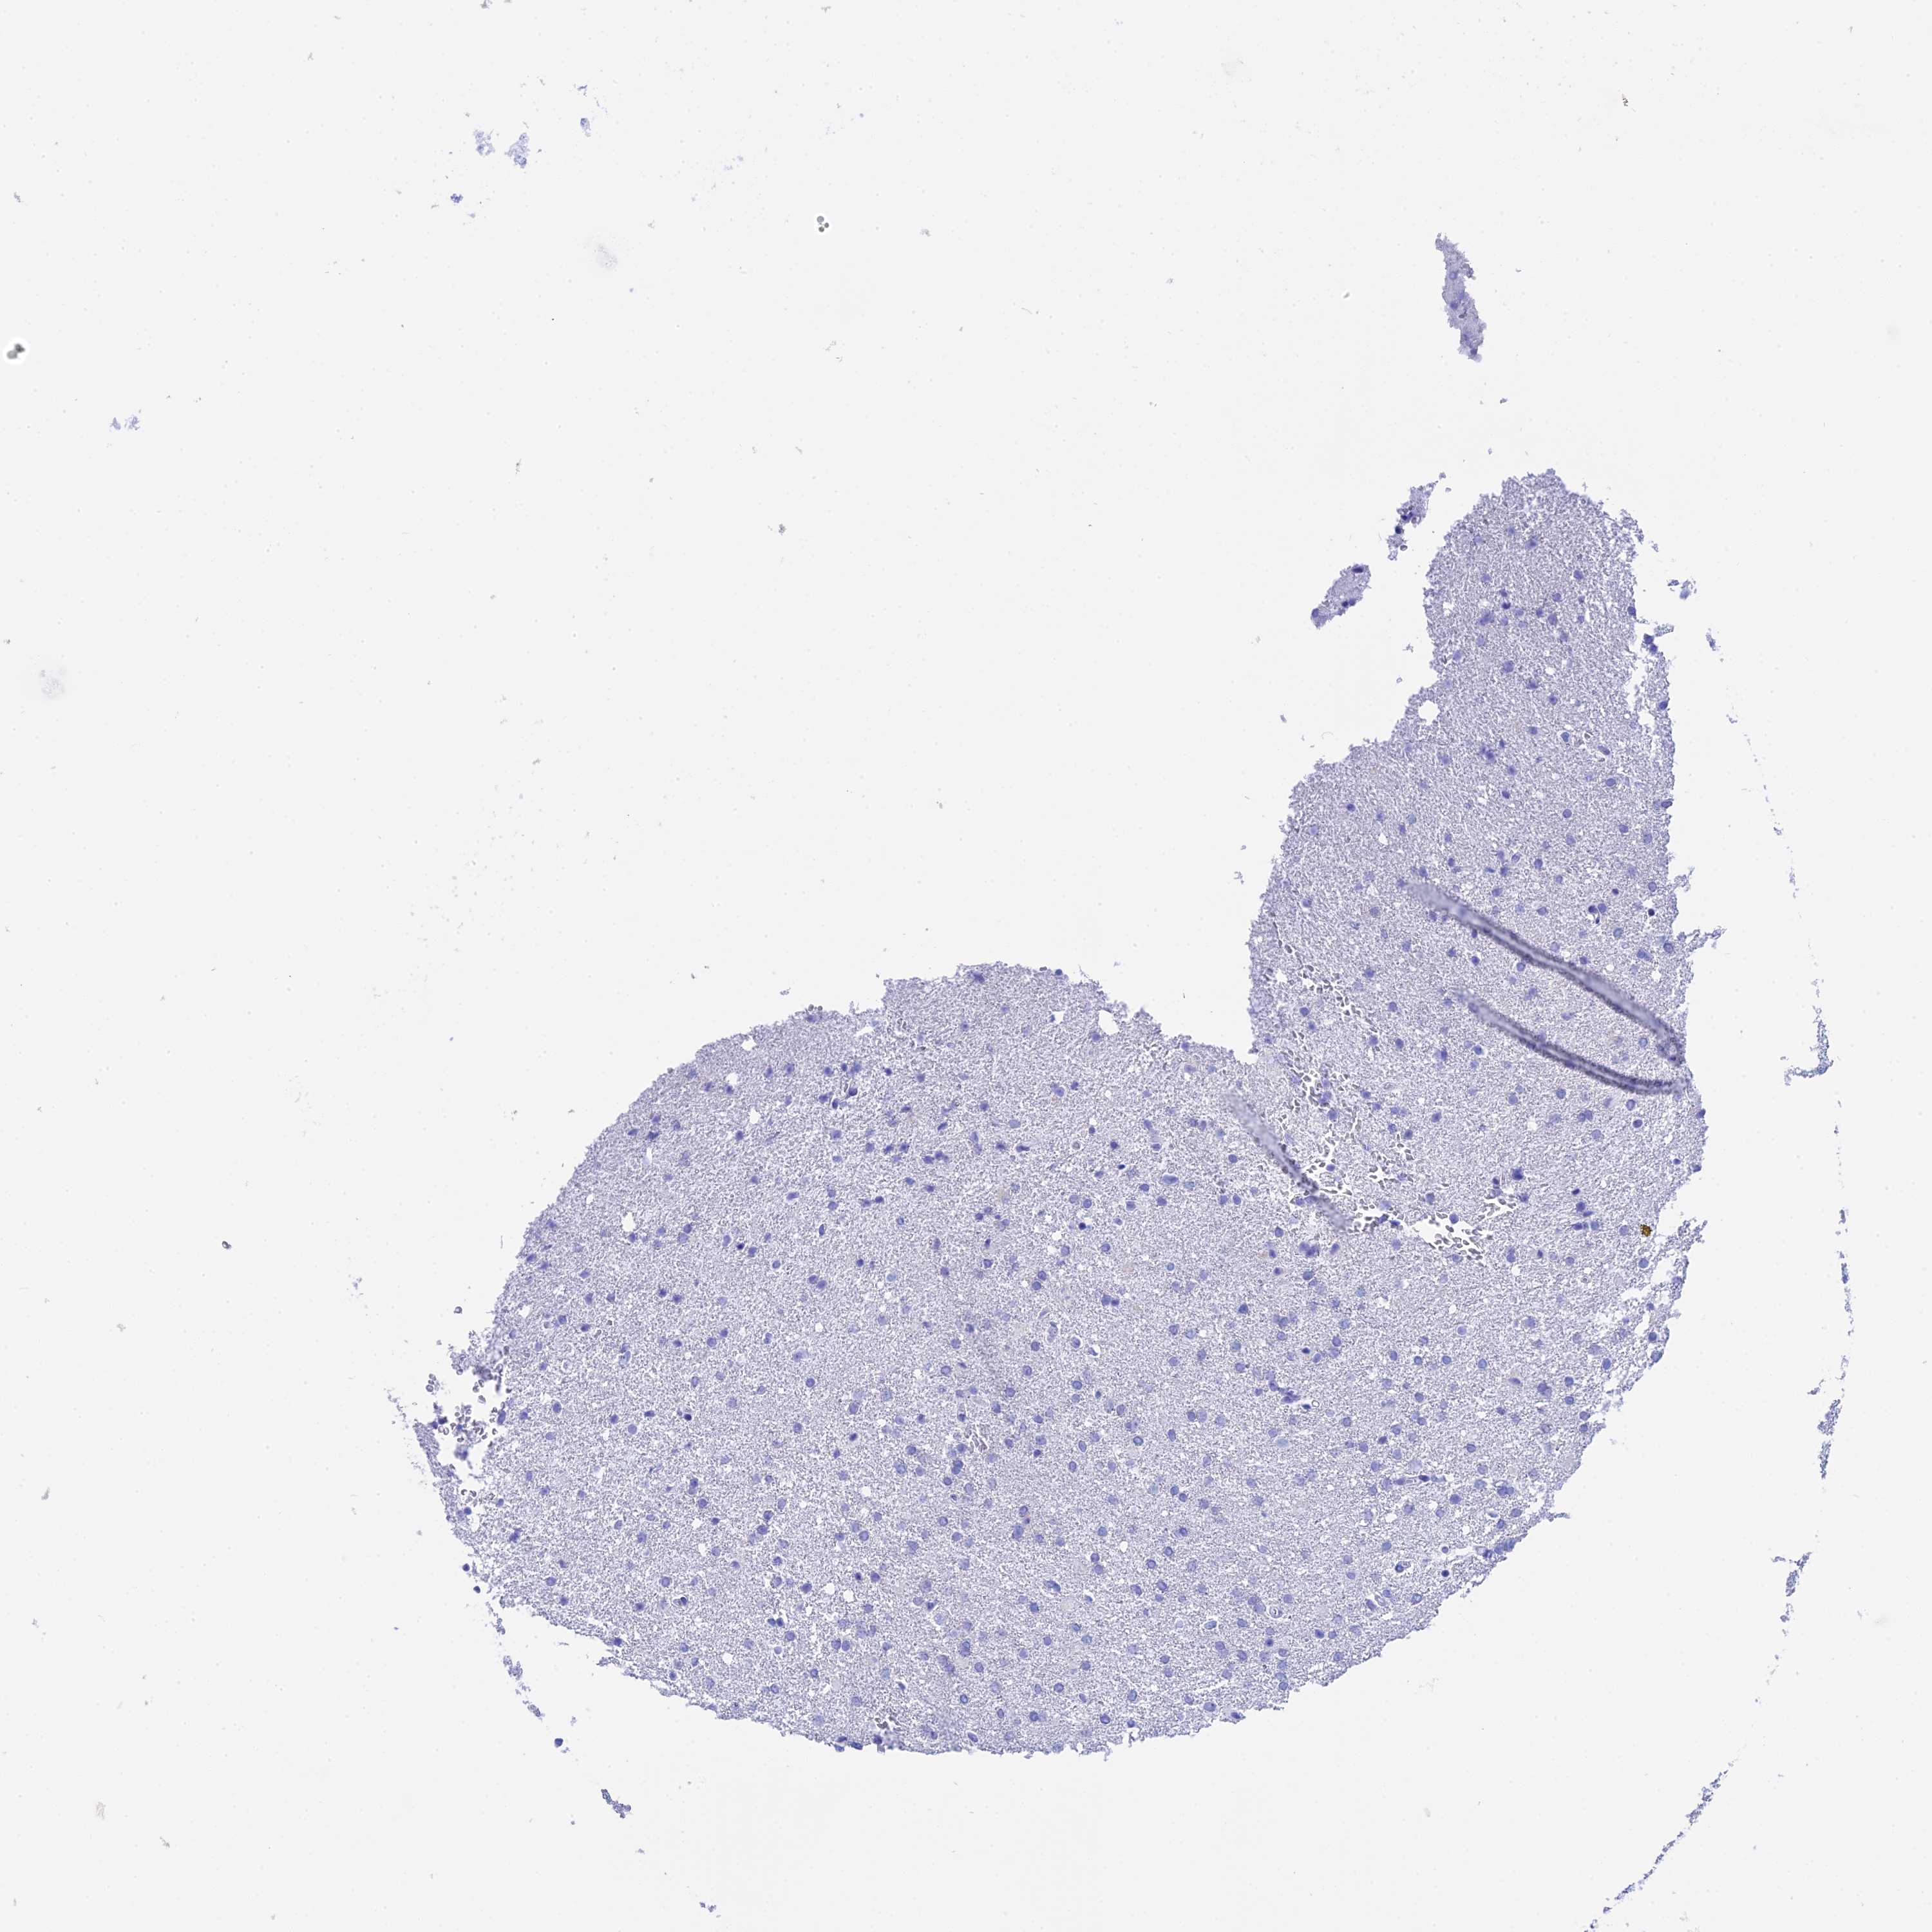

GLIOMA - Protein expressioni

A mouse-over function shows sample information and annotation data. Click on an image to view it in a full screen mode. Samples can be filtered based on level of antibody staining by selecting one or several of the following categories: high, medium, low and not detected. The assay and annotation is described here.

Note that samples used for immunohistochemistry by the Human Protein Atlas do not correspond to samples in the TCGA dataset.

Antibody stainingi

Antibody staining in the annotated cell types in the current human tissue is reported as not detected, low, medium, or high, based on conventional immunohistochemistry profiling in selected tissues. This score is based on the combination of the staining intensity and fraction of stained cells.

Each image is clickable and will lead to virtual microscopy that enables deeper exploration of all samples and also displays staining intensity scores, fraction scores and subcellular localization as well as patient and tissue information for each sample.

Antibody HPA041915

Antibody HPA042513

Staining

High

Medium

Low

Not detected

Intensity

Strong

Moderate

Weak

Negative

Quantity

>75%

75%-25%

<25%

None

Location

Nuclear

Cytoplasmic/membranous

Cytoplasmic/membranous,nuclear

Glioma, malignant, High grade

Glioma, malignant, Low grade